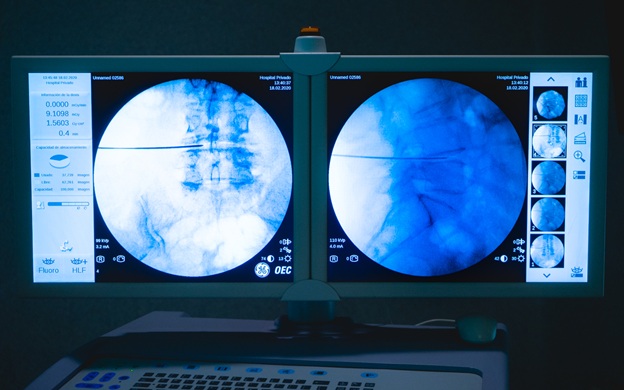

La utilización de las técnicas MISS en un centro médico depende de muchas variables institucionales, como lo son la tecnología y el instrumental disponible. Particularmente Hospital Privado cuenta con aparatos de radioscopia de última generación, sistemas de navegación y técnicos en imágenes, especializados en la patología raquimedular. La razón de la necesidad absoluta de contar con estas herramientas es que la minimización de una ruta de acceso conduce inevitablemente a una visualización más limitada del campo quirúrgico, o a ninguna visualización en absoluto. Por lo tanto, prevalece el uso de imágenes de rayos X para la orientación local, ya que los puntos de referencia anatómicos visuales que alguna vez fueron familiares en condiciones macroquirúrgicas pueden ser indistinguibles u oscurecidos. En algunos casos intraoperatoriamente, es necesario utilizar sistemas de navegación para verificación del “área objetivo” de manera segura.